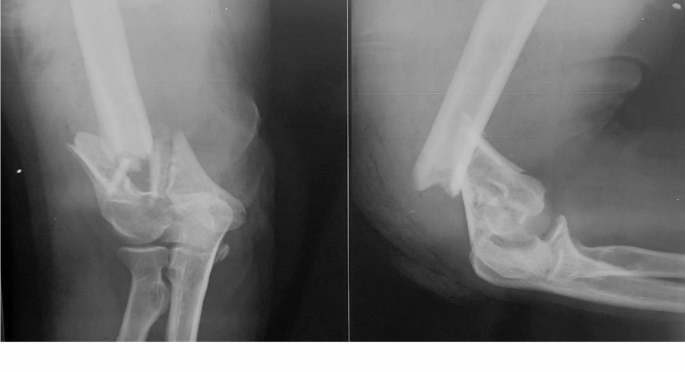

Group A: Internal fixation via the parallel plating method (29 patients). (Fig. 2)

A 47-year-old female patient with a distal humerus fracture.

The patient underwent surgery with the parallel plating method.

a.

Anteroposterior and lateral initial plain radiographs.

-

b.

Anteroposterior and lateral postoperative plain radiographs taken 2 weeks postoperatively.